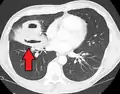

- تصوير الصدر بالأشعة السينية وأخرى

يُصيب الخراج في كثير من الأحيان جانب واحد ويشمل القطاع الخلفي من الفص العلوي والقطاعات القمية من الفص السفلي عند الإستلقاء. وجود بعض المستويات من هواء سائل يؤدي إلى تمزقات في القصبة أو في قليل من الأحيان نمو الغاز وبالتالي تكوين كائن حي.